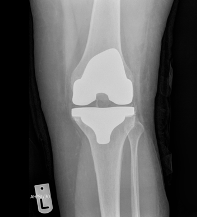

Images of Knee Replacement:

X-Ray of Knee Replacement 1